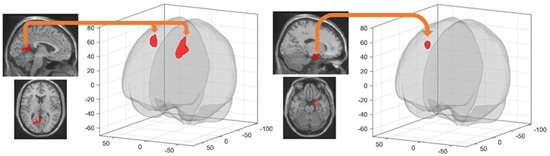

| Left Retrosplenial Cortex | Left Superior Frontal Gyrus | −16 12 48 | 738 | 5.91 | 0.000000 |

| Right Middle Frontal Gyrus | 28 6 56 | 390 | 5.78 | 0.000047 | |

| Right Entorhinal Cortex | Right Superior Frontal Gyrus | 18 24 56 | 228 | 5.25 | 0.001829 |